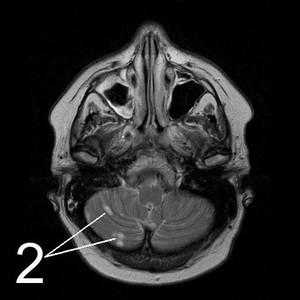

МР-томограммы головного мозга.

1. Киста, возникшая после кровоизлияния в мозг.

2. Кисты мозжечка, возникающие вследствие ишемического инсульта (закупорка сосудов головного мозга).

3. Кистозно-слипчивый арахноидит.